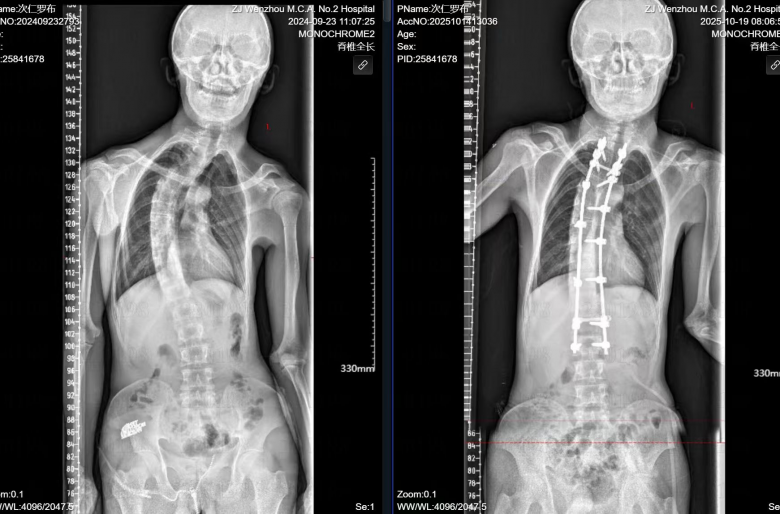

命运的转机出现在去年。温医大附二院副院长吴爱悯在嘉黎县人民医院筛查中发现了小布的情况,决定帮助其挺直腰杆。小布不仅患有严重脊柱侧弯,还存在环枕部畸形等上颈椎问题,若一次性完成所有矫形手术,风险极高,可能危及脊髓功能甚至生命。经过多学科会诊讨论,医疗团队为其制订了“分两步走”的审慎方案。

去年10月,小布首次来温,接受了第一阶段手术——“环枕畸形减压+脑脊液漏修补术+椎管扩大减压术”。这关键第一步,旨在为受压的脊髓和神经“松绑”,重建一个稳定的颅颈交界区,为后续矫形打下坚实基础。

在家康复并休养一年后,小布的身体条件完全成熟,日前他再次来到温州,接受了第二阶段的脊柱侧弯矫形术,最终完成了这场跨越千里的“脊梁工程”。小布激动地说,今后他可以抬头做人,像牦牛一样在高原上奔跑了。